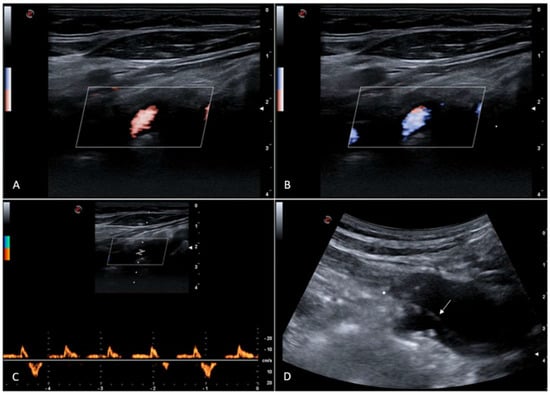

Figure 1. Color Doppler ultrasound shows antegrade (A) and retrograde (B) right vertebral artery flow; Doppler spectral waveform shows intermittent and irregular right vertebral artery flow reversal (C). Innominate artery dissection can be demonstrated ((D), Figure S1), with a dissection flap just near the right subclavian artery origin. It can be supposed that dissection flap irregular movements can cause a sporadic reduction of end-systolic subclavian artery pressure, which could be at the base of the random right vertebral artery flow reversal occurrence. The 73-year-old female patient was asymptomatic at the time of the ultrasound examination; she suffered from spontaneous type A acute aortic dissection with epiaortic arteries involvement and underwent surgical operation 9 years ago. Type A aortic dissection is a life-threatening surgical emergency with a suggested incidence of about 5 per 100,000 person-years, sometimes associated with supra-aortic trunk involvement [1,2,3,4]. Long-term outcomes of this disease are improving over time, and it is known that sometimes false channels remain patent after surgery [5,6]. A previous study reported an aortic dissection extending to the innominate and right common carotid arteries which showed blood passing from the false lumen of the distal right common carotid artery into the true lumen with antegrade flow in the false lumen but reverse flow in the true channel, the latter supplying the subclavian artery [7]. To our knowledge, no previous studies have reported this intermittent flow reversal; therefore, supra-aortic trunks dissection should be considered among the possible causes of vertebral artery flow reversal.